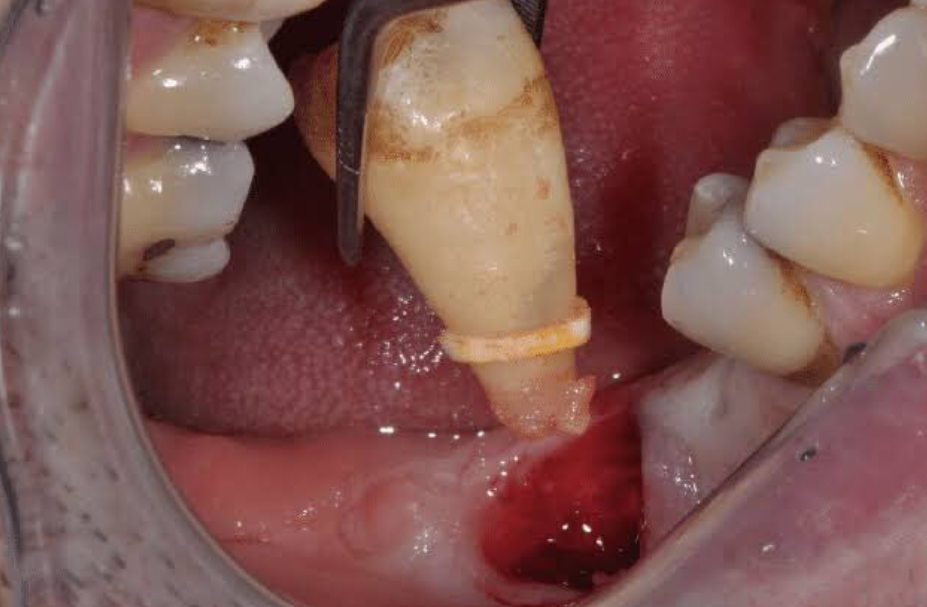

Răng khôn hay còn gọi là răng số 8 thường xuất hiện khi vào tuổi trưởng thành, nằm ở vị trí trong cùng ở mỗi hàm và không có chức năng ăn nhai. Tùy tình trạng mỗi người, có người cả bốn răng khôn mọc và hoạt động bình thường. Tuy nhiên ở nhiều người, răng khôn mọc ở một góc hoặc bị kẹt trong xương hàm khiến đau răng, khó chịu, tổn thương các răng lân cận và gây ra nhiều biến chứng. Vì thế việc nhổ răng khôn là cần thiết để bảo vệ răng, ngăn ngừa bệnh lý, các biến chứng có thể xảy ra và để quá trình ăn uống, sinh hoạt thường ngày không bị ảnh hưởng.

Răng khôn gây ra nhiều biến chứng nguy hiểm nếu không điều trị kịp thời